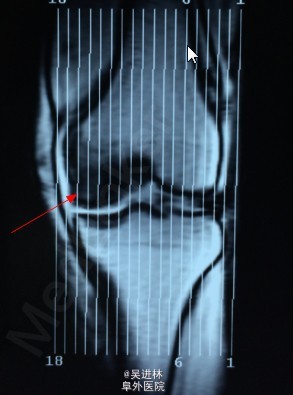

患者6个月前无明显诱因出现左膝关节内侧间隙疼痛,就诊于当地医院,诊断为骨坏死(骨髓水肿易误诊为骨坏死),行左股骨内侧髁开窗病灶清除术。一月前无明显诱因再次出现左膝关节外侧间隙疼痛,无法行走,站立及上下楼梯,无发热,无腰痛,无下肢肿胀,我院诊断为“骨髓水肿”。骨髓水肿发生于单髁是比较少见的,通常累及整块骨头,这个病人不仅在单髁发生骨髓水肿,而且奇怪的是,左侧髁水肿好了之后,外侧髁侧又出现了水肿。